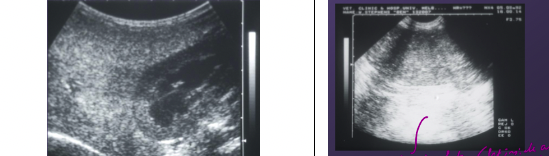

For the images below state which one was taken from in an organ and which one was taken from outside and organ:

Left = irregular in texture, hypoechoic to anechoic. Usually speckled in texture. (outside)

Right = uniform in texture + high echogenicity